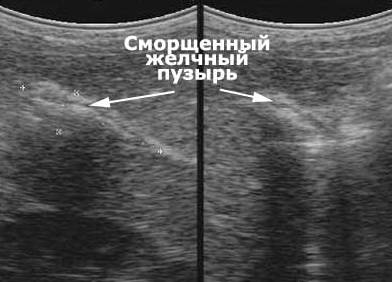

Для уточнения диагноза, как правило, используется методика УЗИ-диагностики, с помощью которой специалист определяет форму и размер пораженного органа. Кроме того, такое исследование позволяет определить текущее состояние этого желчного резервуара. Он может или не работать совсем, или работать с перебоями, может быть сморщенным или находится в нормальной форме. При отключении желчного пузыря в нем никогда нет внутри желчи, и он никогда не способен самостоятельно сокращаться. Кроме такого, такое исследование помогает обнаружить в этом органе опухоли и камни.

Совсем неработающий желчный пузырь на снимке будет не виден. В подпеченочной области будет заметно лишь небольшое темное пятно.

Если же в этом внутреннем органе еще есть жёлчь, то этот его участок будет выглядит более светлым, а над этим пятнышком будет видна плотная стенка. Спавшийся желчный пузырь рассмотреть на снимке практически невозможно. Если орган имеет сморщенность, то контуры такого желчного пузыря будут неправильными и неровными.